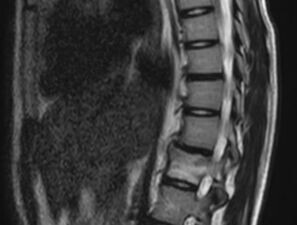

Ein 16-jähriges Mädchen mit Rückenschmerzen und Kyphose

Anfänglich starke Rückenschmerzen, obwohl kein Trauma vorangegangen war, und 9 Monate später eine neu aufgetretene Hyperkyphose der Brustwirbelsäule mit zunehmenden Schmerzen. Wie lautet Ihre Diagnose?